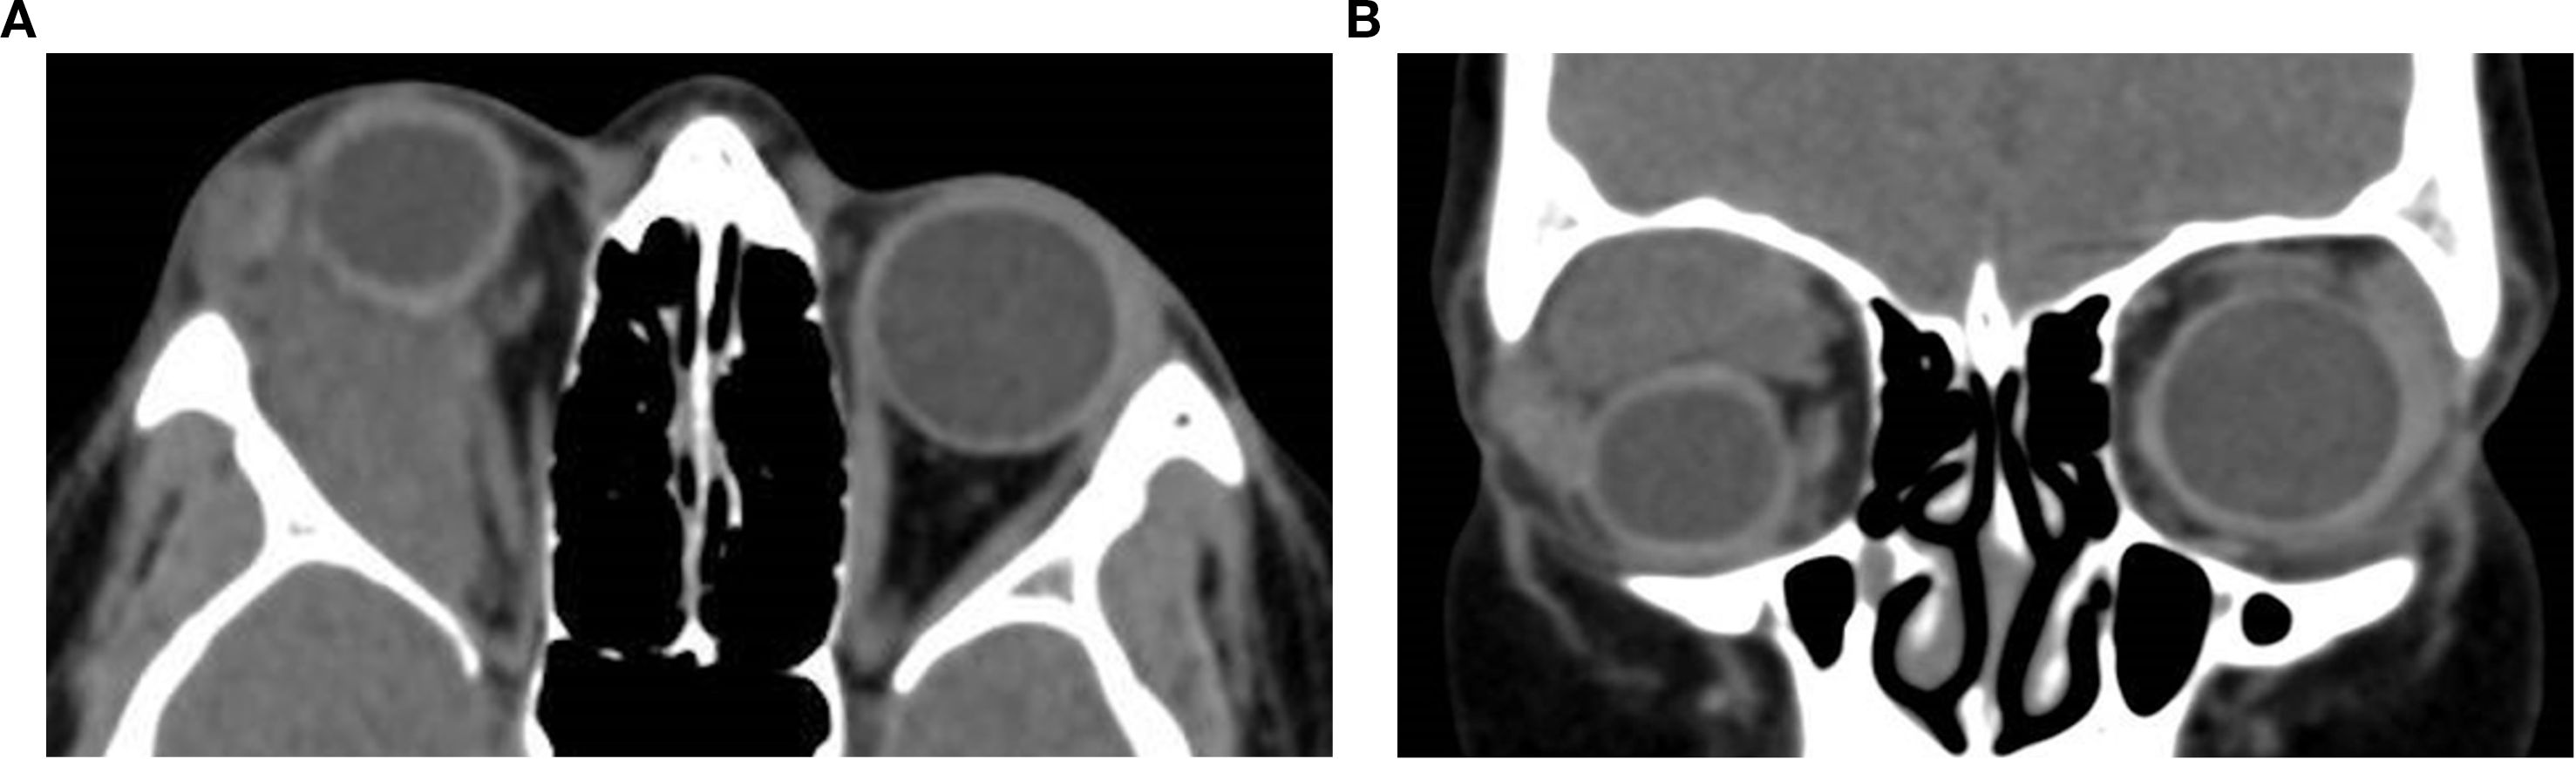

Orbital masses include a diverse spectrum of benign, malignant, inflammatory, and vascular lesions in pediatric and adult patients. Accurately diagnosing the type of lesion is critical, as management strategies differ significantly. Advanced imaging is therefore essential, and computed tomography (CT) is central to orbital evaluation. We reviewed the literature to synthesize evidence on CT features across common orbital pathologies and correlated imaging with clinical presentation to emphasize diagnostic relevance. CT characteristics are summarized for vascular lesions (cavernous venous malformation, lymphatic malformation), inflammatory conditions (orbital myositis, dacryoadenitis), benign lesions (dermoid cyst, pleomorphic adenoma), and malignant lesions (lacrimal gland lymphoma, adenoid cystic carcinoma, rhabdomyosarcoma). We present characteristic patterns of location, morphology, enhancement, and bone change, with practical discriminators and common pitfalls to aid differentiation. When used alongside clinical context, CT remains a preferred modality in many clinical settings due to its rapid acquisition, wide availability, and reliable depiction of bone and calcifications. It supports accurate diagnosis and informed management decisions in time-critical settings. This review provides a structured reference for interpreting CT findings across a wide range of orbital disease.